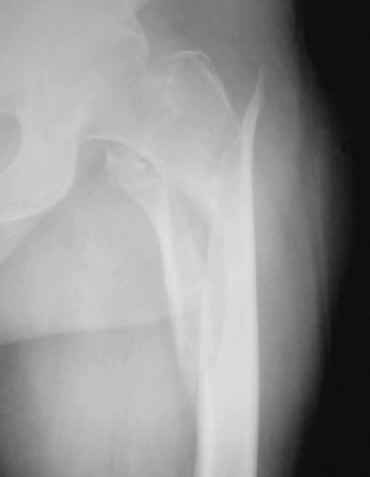

[Ortho] проксимальный отдел бедра

уважаемые коллеги,помогите определиться с тактикой лечения больной:бабушка 72г.с

чрезвертельно_подвертельным переломом и кучей соматических проблем(диабет 2

типа,аг,ревматоидный полиартрит и т.д)находится на скелетном вытяжении.только что стали

внедрять у себя блокирующий остеосинтез.какие мнения?